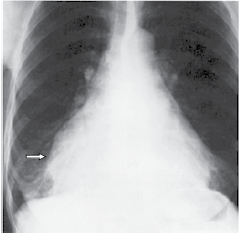

Mulher, 50 anos, é encaminhada ao cardiologista para avaliar paciente com cansaço aos esforços. Realizou a seguinte radiografia, no Pronto-Socorro, uma semana antes:

A seta indica qual estrutura?

Mulher, 50 anos, é encaminhada ao cardiologista para avaliar paciente com cansaço aos esforços. Realizou a seguinte radiografia, no Pronto-Socorro, uma semana antes:

A seta indica qual estrutura?